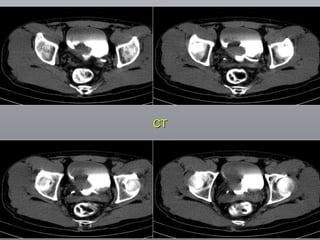

Câncer de Bexiga Estudos de imagens Diagnóstico Ultrassonografia Urografia excretora Estadiamento CT RNM Rx tórax  Cistoscopia + biópsia + biópsias randomizadas

CT